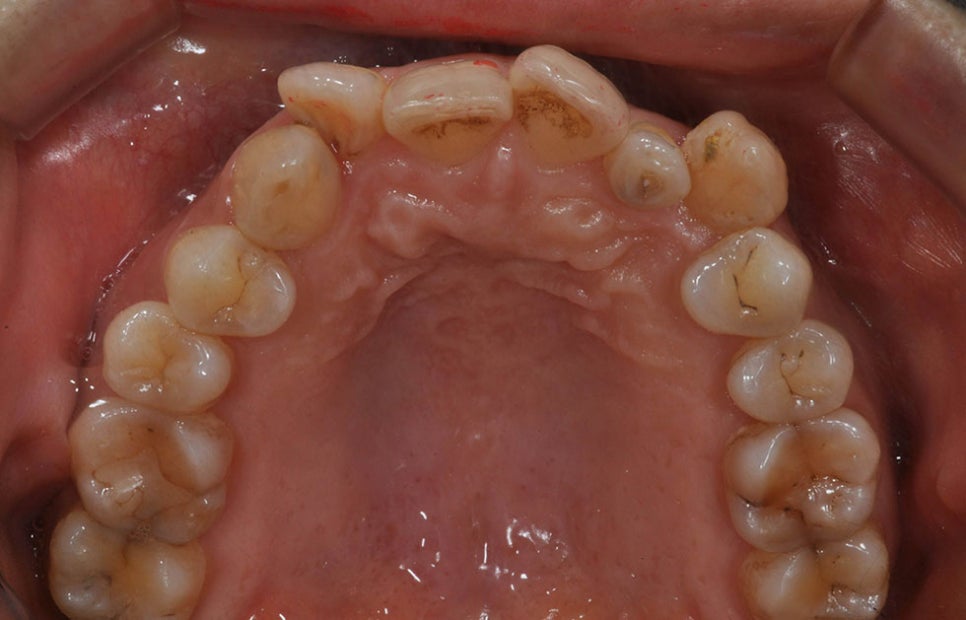

부정교합을 치료하는 방법, 교정

치아가 고르지 않거나 치열이 틀어져

상악과 하악이 딱 들어맞지 않는 상태를

부정교합이라고 합니다. 부정교합은

개인의 건강뿐 아니라 삶의 질을

떨어트리는데 치아 위생 관리가 어려워

충치나 잇몸 질병이 자주 발생하고,

음식을 제대로 씹기 어려워 만성 소화

장애에 시달리기도 합니다. 또한 발음

장애 및 턱관절 장애 등을 겪기도 합니다.

보기에 좋지 않다는 이유로 자신감이

떨어지는 경우도 있습니다. 심한 경우

대인기피증이나 우울증 등 심리적인

질병도 일으킬 수 있습니다.

이러한 부정교합을 치료하는 대표적인

방법이 치아교정입니다. 치아교정은

일정한 힘을 지속적으로 가하면 이동하는

치아의 특성을 이용하는 치료법으로

교정 장치처럼 일정한 힘을 가해 치아의

위치를 원하는 곳으로 이동시킴으로써

틀어진 치열을 교정합니다. 이를 통해

씹기, 발음 등 치아 기능을 보완하고

치아 위생 관리가 수월해질 수 있습니다.